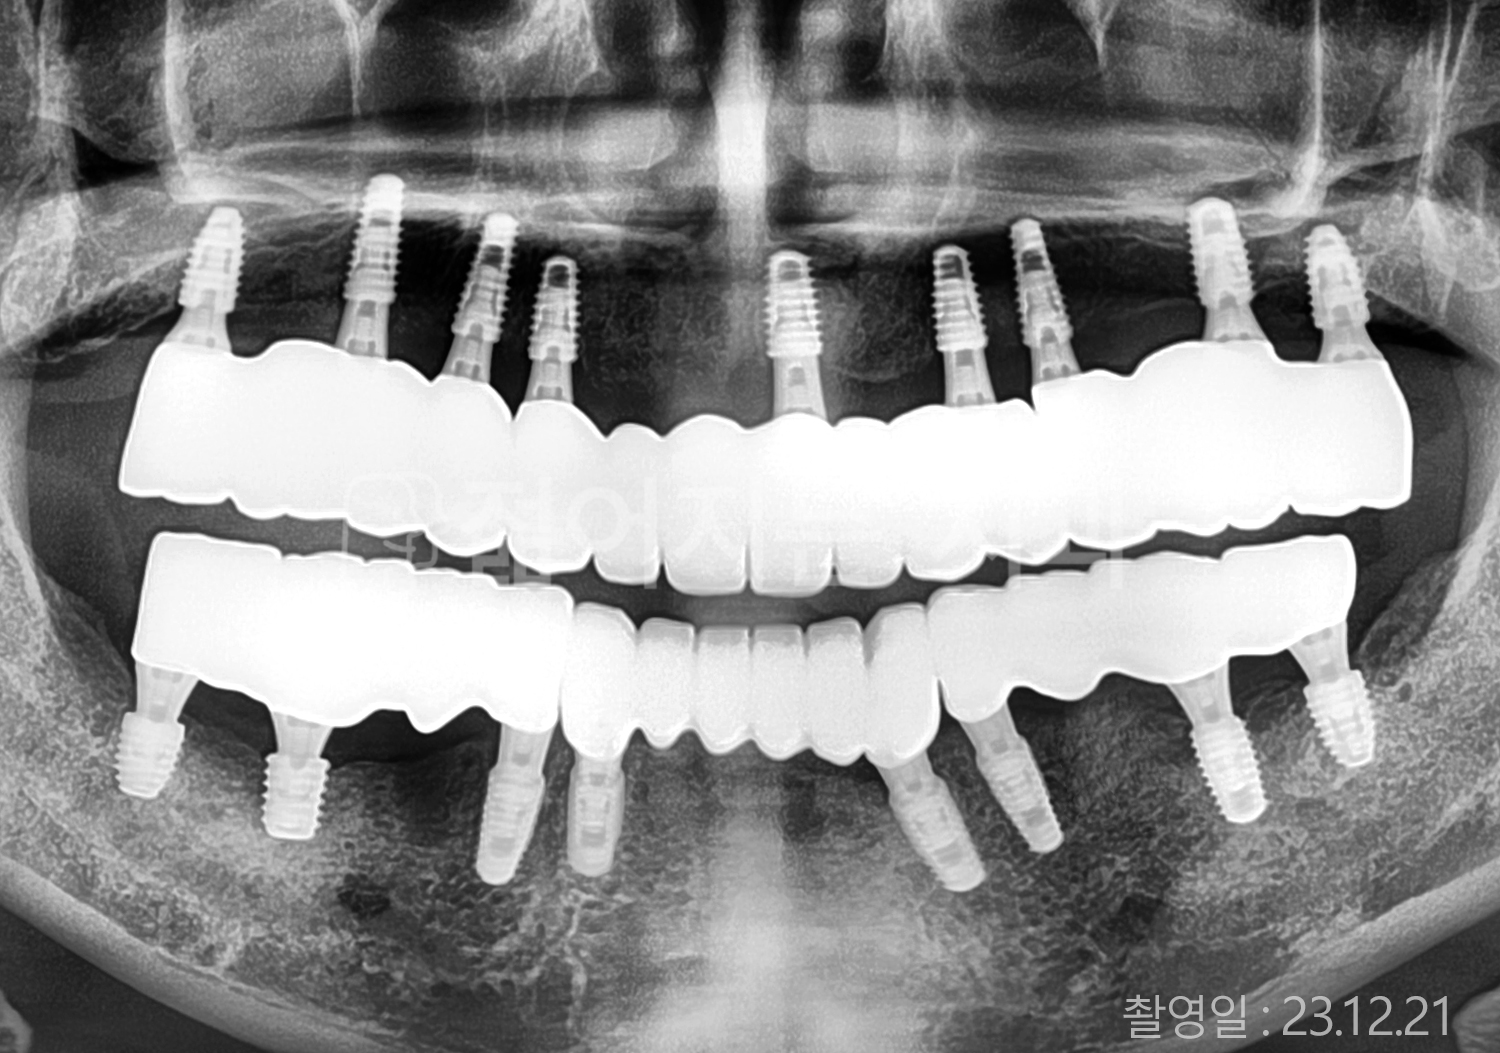

• 60대 전체치아 10개 이상 임플란트